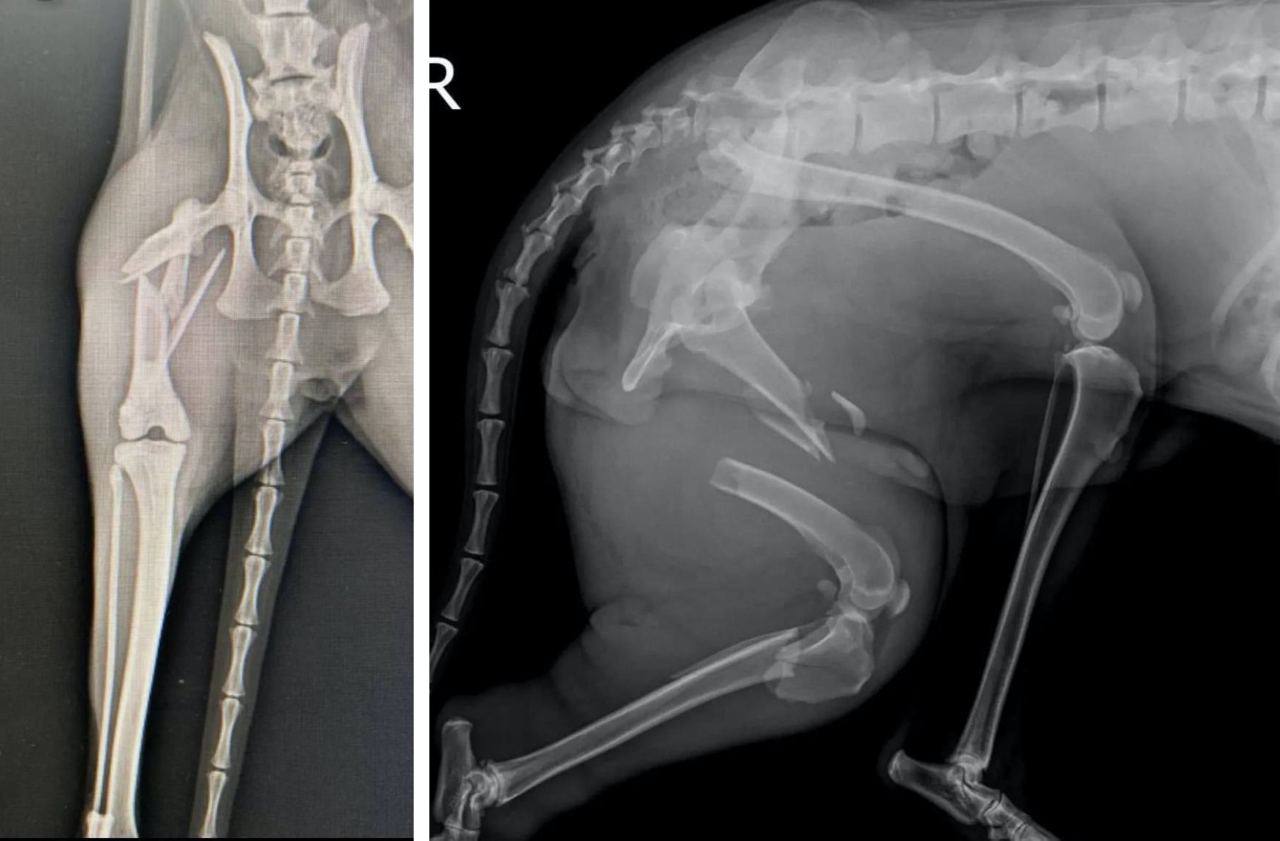

Истончение костей у кошек: причины и решения